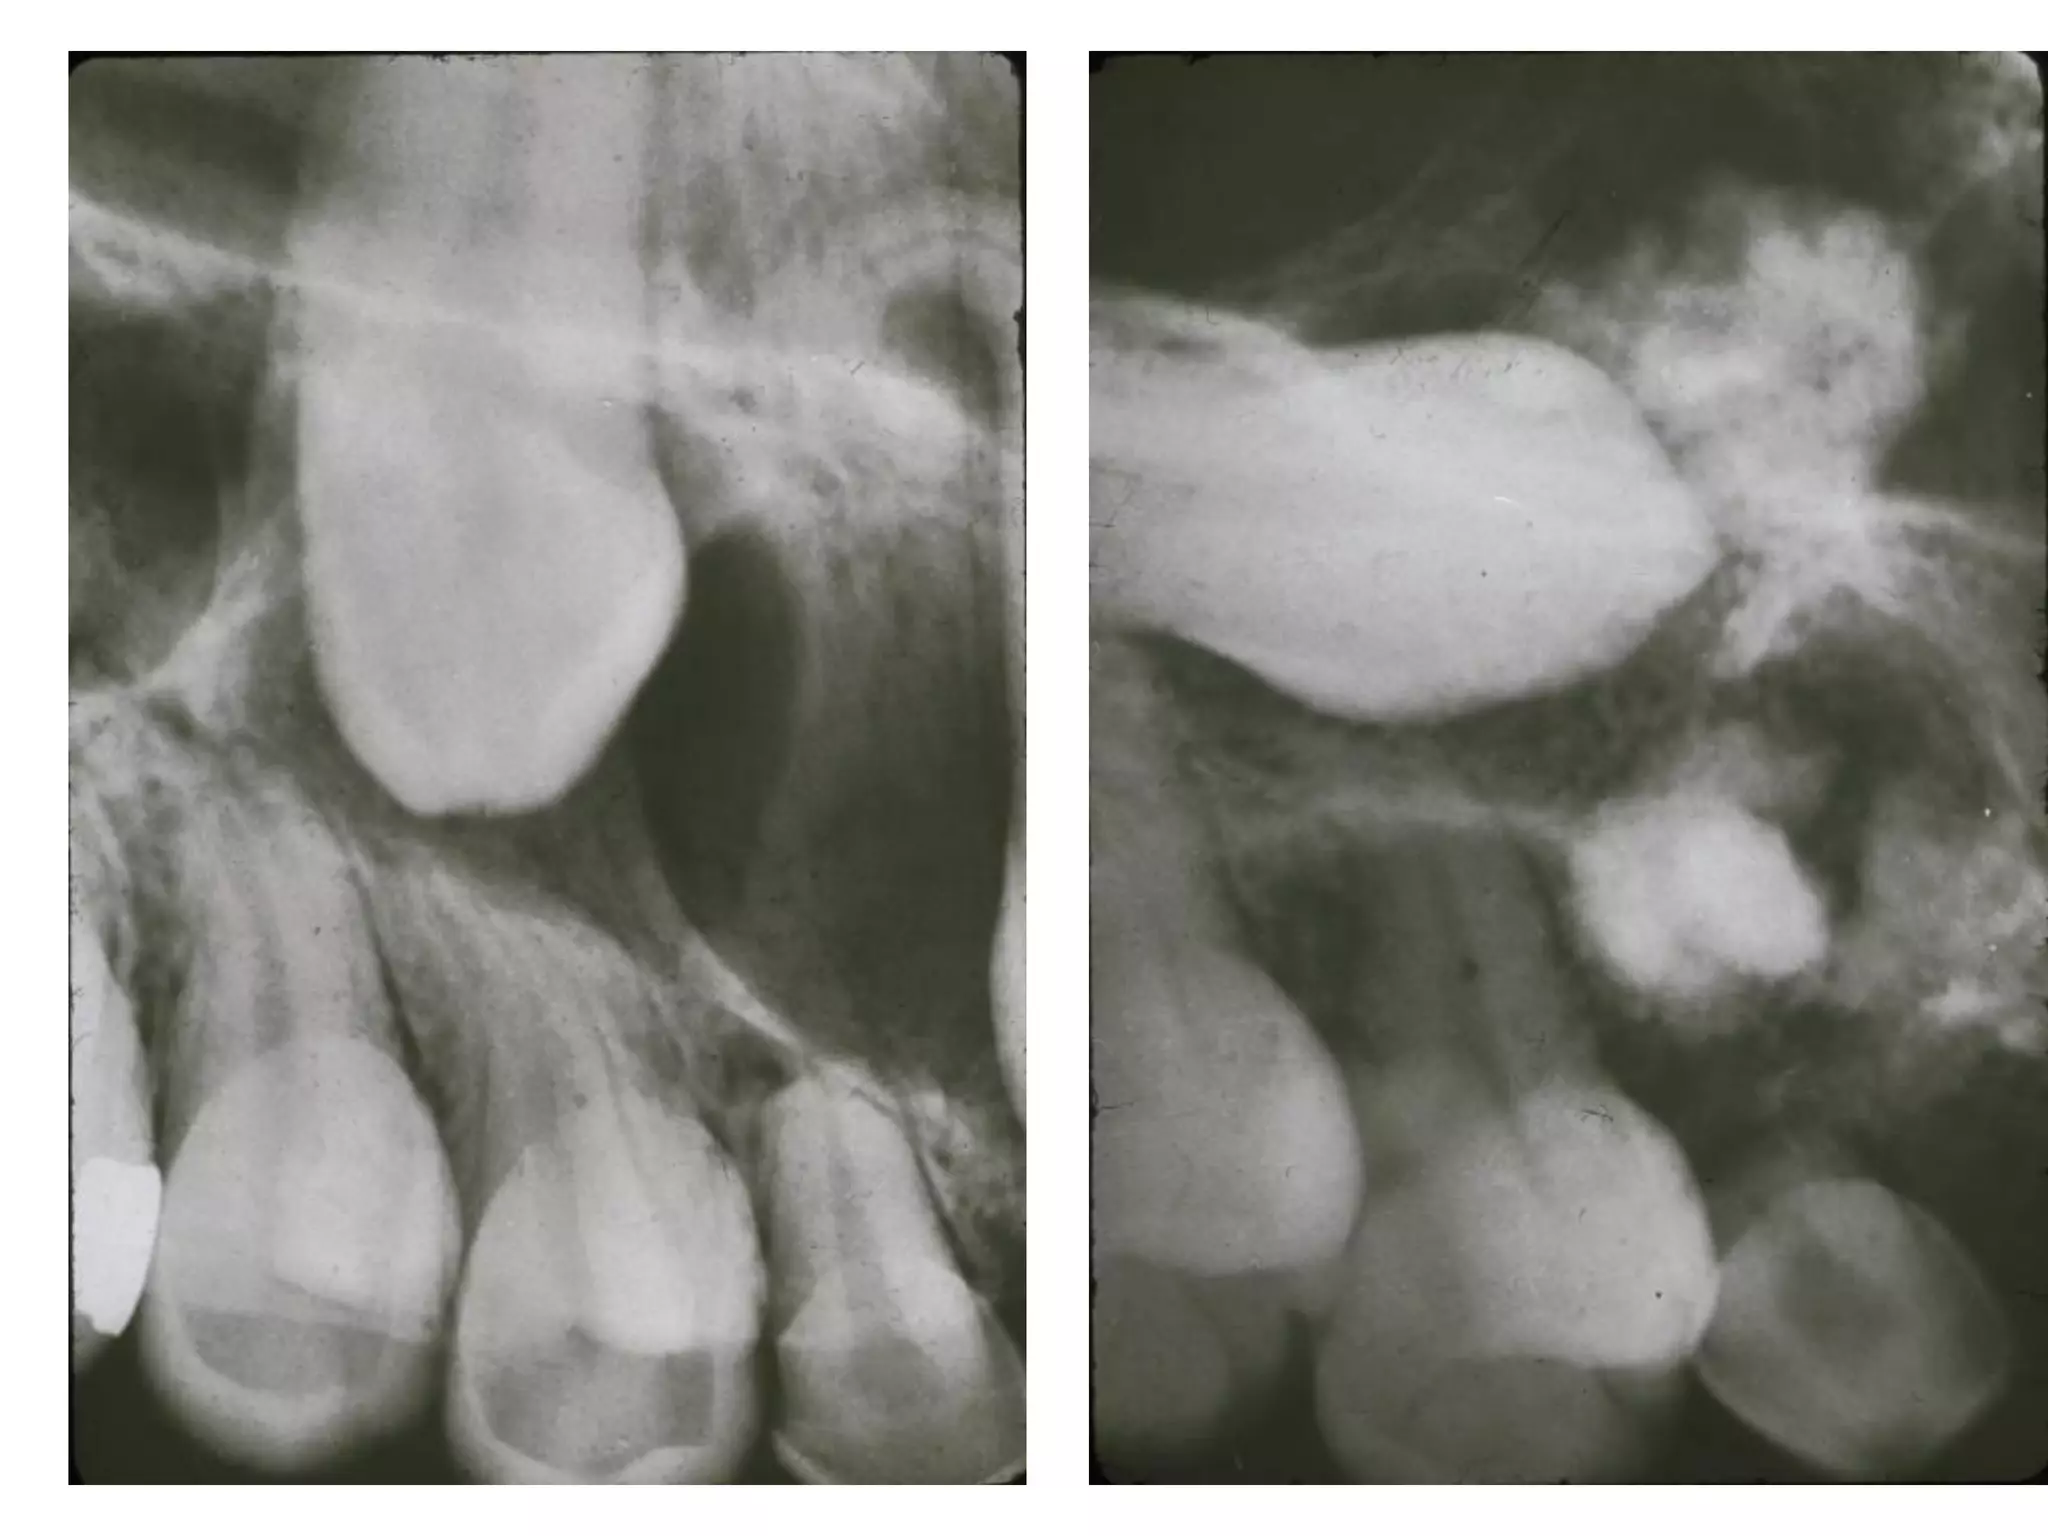

U sôïi men (Ameloblastic Fibroma)

Laâm saøng:

 U do raêng hoãn hôïp

thöïc söï thöôøng gaëp ôû

ñoä tuoåi 10-20, trung

bình 14.

 Nam > nöõ.

 Gaàn 70% vuøng R sau

HD.

X quang:

 Thoâng thöôøng, moät hoác hoaëc nhieàu hoác thaáu quang.

 Giôùi haïn roõ, bôø coù theå xô cöùng.

 50% keát hôïp vôùi raêng ngaàm.

Giaûi phaãu beänh:

 Goàm toå chöùc trung moâ giaøu teá baøo gioáng nhuù

raêng nguyeân thuûy laãn vôùi bieåu moâ taïo raêng

ñang taêng sinh.

U raêng-sôïi-men

Ameloblastic Fibro-odontoma

 Ñöôïc xaùc ñònh laø u vôùi caùc ñaëc ñieåm chung

cuûa moät ameloblastic fibroma nhöng chöùa

men vaø ngaø.

 Moät soá nhaø nghieân cöùu cho raèng thöïc theå naøy

laø moät giai ñoaïn trong söï phaùt trieån cuûa moät

odontoma; tuy nhieân, haàu heát ñoàng yù raèng u

phaù huûy tieán trieån naøy laø taân sinh thaät söï.

 Tuoåi: nhieàu nhaát töø 5-12, trung bình 10 tuoåi.

 Vò trí: thöôøng gaëp ôû vuøng raêng sau cuûa 2

haøm.

X quang: thöôøng laø 1 hoác thaáu quang roõ hoaëc

hieám hôn laø nhieàu hoác thaáu quang vôùi caùc

chaát canxi hoùa caûn quang. Do ñoù coù theå cho

hình aûnh hoãn hôïp vöøa thaáu quang vöøa caûn

quang.

 Thaønh phaàn moâ meàm gioáng ameloblastic

fibroma. Thaønh phaàn canxi hoùa goàm caùc oå

men, söï hình thaønh ngaø coù moái quan heä chaët

cheõ vôùi caáu truùc bieåu moâ.